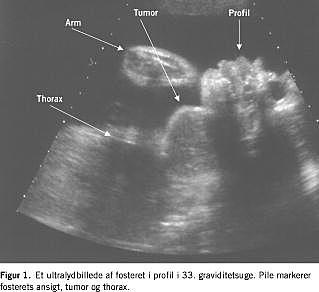

I. En 40-årig, gravid kvinde blev henvist til Rigshospitalet på grund af en 2 cm stor tumor på fosterets hals opdaget ved en 18-20-ugers gennemskanning. Tumoren voksede hurtigt og målte 54 × 48 × 56 mm i uge 33 (Figur 1 ). Fra uge 29 observeredes der tiltagende polyhydramnios som udtryk for afklemning af øsofagus, og der blev foretaget flere aflastende amniocenteser. Ved ultralydsundersøgelser og MR-skanninger i uge 34 fandt man en tumor, der var velafgrænset og heterogen uden store kar, målte 94 × 43 × 60 mm og var beliggende på højre side af halsen (Figur 2 ). Øsofagus og trachea kunne ikke ses og ansås for at være komprimerede. Ved en tværfaglig konference vurderede man, at der var risiko for, at fosteret ville have en kompromitteret luftvej ved fødslen, og der blev planlagt sectio med EXIT-procedure i uge 36 med henblik på at bevare placentafunktionen og etablere frie luftveje før afnavling. Generel anæstesi blev indledt med tiomebumal-fentanyl og vedligeholdt med sevofluran og fentanyl. Uterus blev relakseret med sevofluran, diclofenac og atosiban (oxytocin-receptorantagonist). Blodtabet blev skønnet til at være på en liter, og anæstesien varede ca. 90 minutter og forløb ukompliceret.